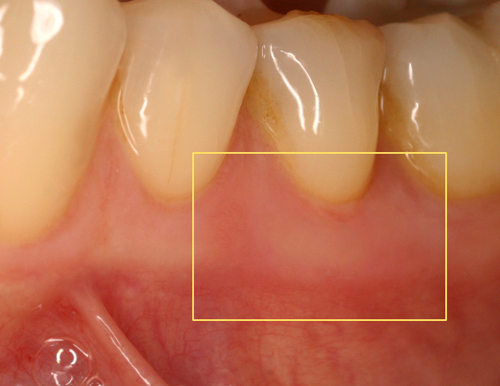

Fig.20 Présence de deux aphtes douloureux

Par exemple, sur des aphtes douloureux (fig. 20) un rayonnement laser est rapproché progressivement jusqu’à une disparition quasi complète des sensibilités (fig. 21).